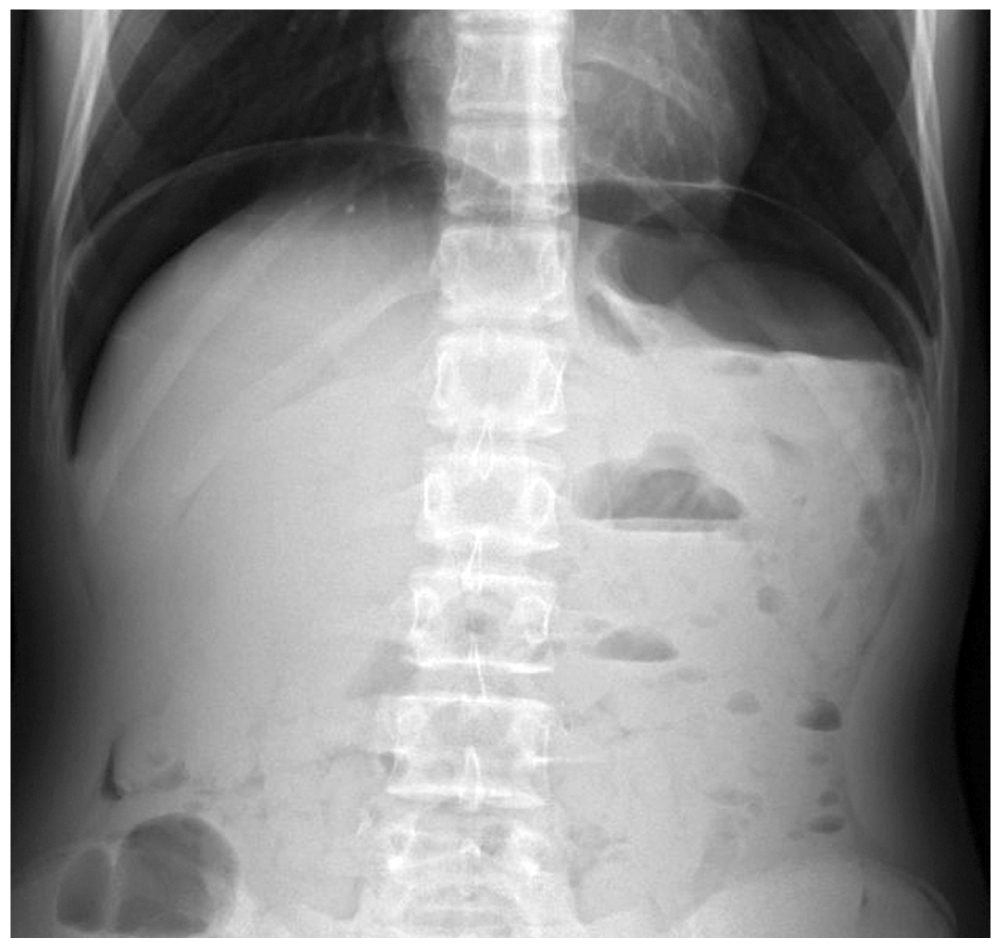

При пальпации живот болезненный во всех отделах, симптомы раздражения брюшины положительные. Температура тела 37,6 ℃. По клинико-лабораторным данным выявлены признаки дегидратации (гематокрит 50,2%, концентрация лактата в плазме крови 2,9 ммоль/л, концентрация К+ в плазме крови 5,8 ммоль/л, концентрация Cl− в плазме крови 113 ммоль/л), количество лейкоцитов в периферической крови 9,2×109/л. При проведении УЗИ ОБП в мезогастральной области обнаружено большое количество свободного газа; по боковым поверхностям живота определялись расширенные петли кишечника с утолщённой стенкой и жидкостным содержимым в просвете кишечника. Перистальтика вялая, маятникообразная. При ОР ОБП выявлен свободный газ в брюшной полости (рис. 2).

Рис. 2. Клинический случай № 2: обзорная рентгенограмма органов брюшной полости.

Fig. 2. Clinical case 2. Overview radiography of the abdominal organs.